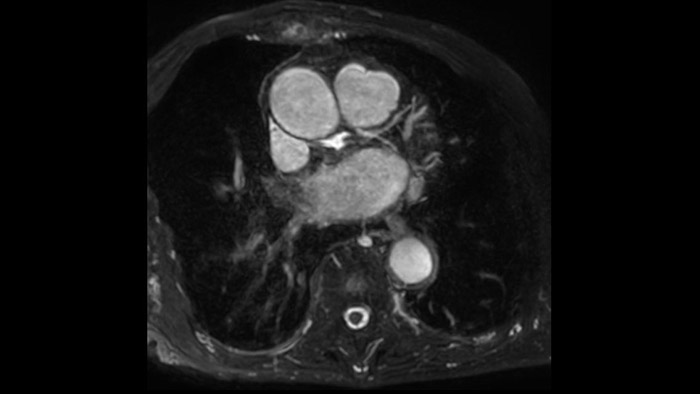

A utilidade do diagnóstico e prognóstico da RM cardíaca está a aumentar. Avalie a anatomia e função do coração utilizando aquisições cine, adquira informações sobre a perfusão e viabilidade do tecido cardíaco, visualize potenciais edemas com sequência de sangue escuro, aceda e quantifique mesmo a caracterização do tecido com a CardiacQuant.

IntelliSpace Portal MR Caas7,8 A solução de pós-processamento 4D Flow permite a geração de reconstruções de volume 3D, para visualizar e avaliar o fluxo sanguíneo em estruturas cardiovasculares, incluindo válvulas cardíacas, câmaras e vasos, com base nas imagens de RM 4D Flow cardiovascular.